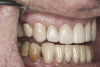

(38.) Postoperative right anterior, close-up view.

Figure 38

(39.) Postoperative anterior, close-up view.

Figure 39

(40.) Postoperative left anterior, close-up view.

Figure 40

Based on examination of the mounted models, it was decided to treat the patient in centric relation and an additive equilibration approach was used to idealize the planes of occlusion. On the articulator, the patient’s first point of contact in centric relation was the starting point and an additive equilibration technique was implemented, building the teeth to meet ideally at the patient’s first point of contact. A diagnostic wax-up was completed on the mounted models to determine where the anterior and posterior teeth needed to be in space. A template from the wax-up was used to fabricate the anterior provisional restorations. The anterior teeth were restored with full-coverage restorations, creating ideal stops between the lower incisal edges and upper cingulums. The maxillary incisal edges were placed to provide proper phonetics and an acceptable esthetic outcome, while still working within the envelope of function. All of these parameters are worked out in the provisionals prior to moving forward with definitive restorations. With the anterior provisionals in place, posterior composite tops were bonded to his existing dentition, creating ideal centric stops on the posterior teeth. The anterior and canine guidance was developed, resulting in immediate separation of the posterior teeth during all excursive movements (Figure 17 through Figure 28). Once the author and patient were happy with the function, esthetics, phonetics, and comfort of the provisionals, an impression of the approved provisionals was taken and sent to the laboratory to use as a guide in the fabrication of the final anterior crowns. With the final restorations delivered, the patient was extremely happy with his new smile. Most importantly, proper anterior and canine guidance in harmony with his envelope of function was achieved, which resulted in comfortable function and immediate separation of the posterior teeth during protrusive and lateral excursions (Figure 29 through Figure 42).